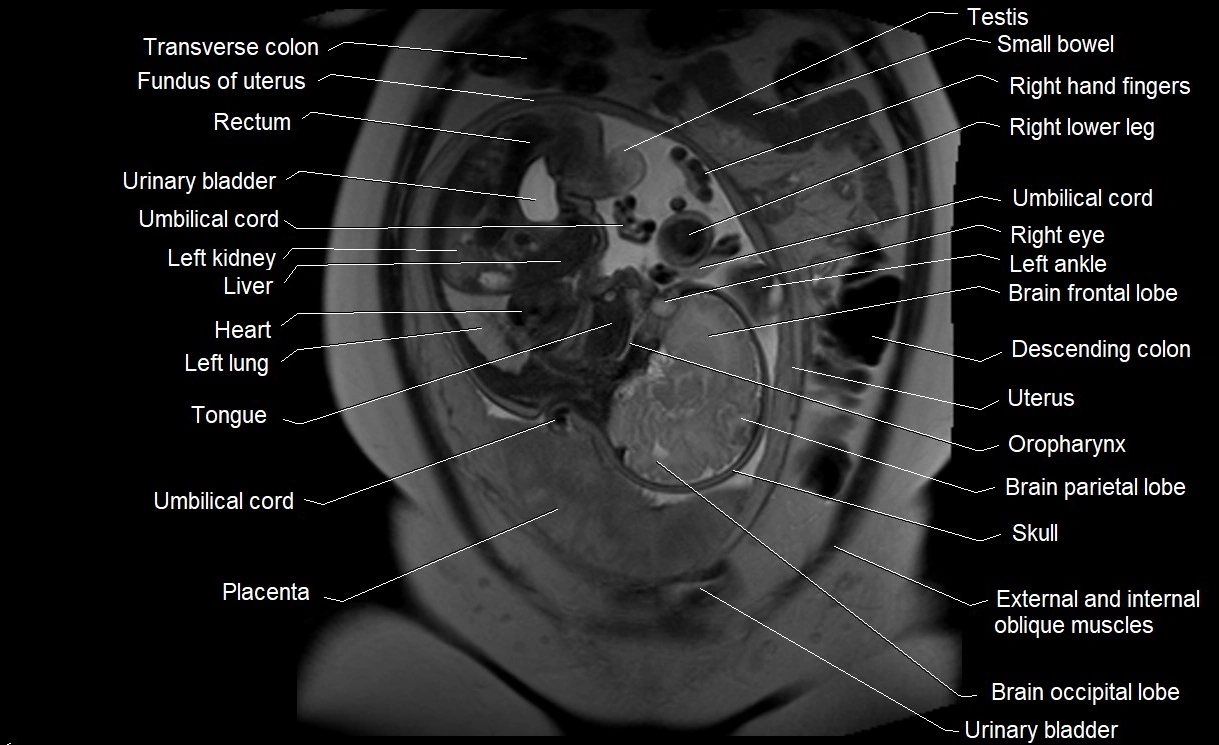

MRI Appearance

T2 HASTE (T2 GRE):

• Amniotic fluid shows very bright hyperintense signal

• Provides natural contrast against fetus and placenta

• Small particles (vernix) may appear as scattered hypointense foci within bright fluid